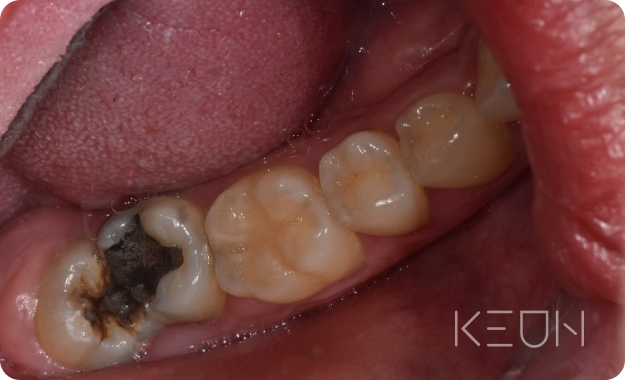

충치&신경 재치료.

충치 재치료

처음 충치 치료를 할 때 대부분 보철물을 씌우는 충전치료를 하는데요, 치아와의 틈이나 경계 없이 치료가 이루어집니다. 보철물의 수명은 관리에 따라 다르지만 보통 5~8년 정도로 시간이 지나면 재료도 오래되고, 치아의 틈 사이로 음식물이 낄 수 있습니다. 제대로 제거가 되지 않으면 2차 충치가 생기기도 합니다. 또한 입안에는 항상 세균이 상주하고 있어 관리가 소홀해지면 충치가 발생하기 쉽습니다.

- Before

- After